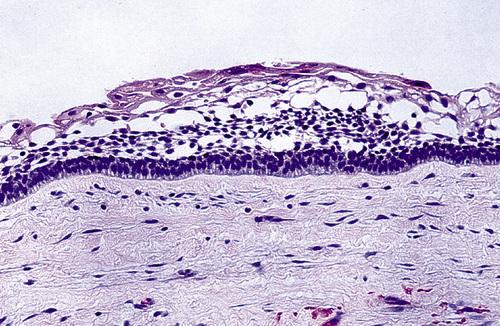

Histopathologic Features

- thin, friable wall, difficult to enucleate in one piece

- cystic lumen may contain either:

- clear liquid similar to a transudate of serum

- cheesy material consisting of keratinaceous debris

- epithelial lining of stratified squamous epithelium

- luminal surface of flattened parakeratotic epithelial cells

- basal layer composed of a palisaded epithelial cells

The epithelial lining is 6 to 8 cells thick, with a hyperchromatic and palisaded basal cell layer. Note the corrugated parakeratotic surface.

odontogenic keratocyst (OKC)